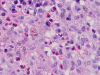

At scanning magnification (Panel A), the lung parenchyma is replaced by some coalescing fibrous nodules. The degree of involvement is variable at different fragments (Panel B and C). In the less affected areas, there are some fibrotic thickening of the septa (Panel C). In some areas, the changes are minimal and the pleural appear to be uninvolved (Panel D and E). In low to medium magnifications, these nodules of fibrosis contains a large number of hemosiderin laden macrophages (Panel F and G) admixed with fibrous tissue. The diagnostic tissue, however, is present in areas with increased cellularity. In these areas, there is a background of cells with a moderate amount of cytoplasm and bland nuclei. Some of these nuclei have kidney shape (arrow in Panel H). In some areas, many of the nuclei have a deep nuclear groove that resemble a coffee bean (arrow in Panel I). In the third type of areas, the nuclear grooving is not distinct (Panel J). Prominent eosinophilic infiltrations are almost always present. Immunohistochemistry on CD1a revealed many positive cells (Panel L). Also present in the specimen are multiple small blood vessels with thickened intima (Panel K). A Movat pentachrome stain demonstrates an internal elastic layer in these vessels and confirms that these are arteries (Panel M and N).

Pathologically, PLCH can be broadly divided into an early or cellular stage and a late or fibrotic stage. Demonstration of LCs is of critical importance for a correct diagnosis. The morphology of LCs is similar to LCH in other organs. LCs are characterized by a deep nuclear groove which lead to “coffee bean-shaped” or “kidney-shaped” nuclei. In most cases, the level of atypia and pleomorphism is low. A moderate amount of amphophilic to weakly eosinophilic cytoplasm is present. The cytoplasmic membrane is indistinct. Eosinophils and chronic inflammatory cells, varying from scant to abundant, are present. Except for a scant frankly pleomorphic cases, the level of pleomorphism and atypia is minimal to low. Eosinophilic abscesses with central necrosis may be present. Immunohistochemically, LCs are similar to their normal counter parts and are positive for CD1a and S100. At the ultrastructural level, Birbeck granules can be demonstrated. For most cases, the diagnosis can be established by histopathologic criteria but these additional features help to confirm the diagnosis.